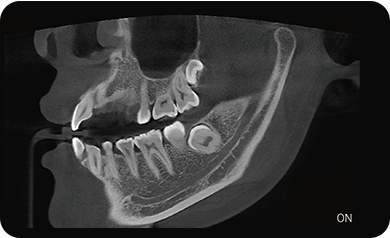

局部超清显示、 移动视野摄片

真人正侧位投影,实现CT成像区域无极可调

可根据临床需求任意调整成像区域大小实现局部超清三维显示

临床样片